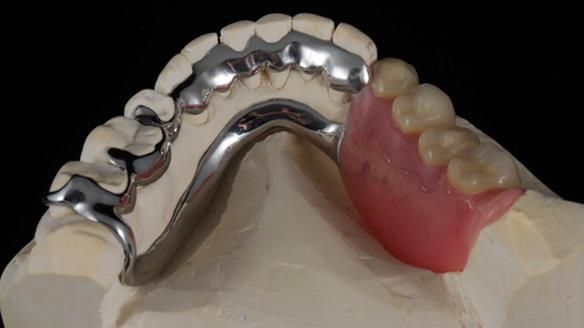

Welcome to Newsletter 61. In this edition, I walk through the process of creating and fitting a metal based lower partial denture for Joyce, a fit and healthy 76 -year-old woman.This issue shows the complete protocol workflow for achieving an exceptionally well-fitted and aesthetically good RPD.

Welcome to Newsletter 61. In this edition, I walk through the process of creating and fitting a metal based lower partial denture for Joyce, a fit and healthy 76 -year-old woman.

The missing lower right teeth to be replaced with a metal based partial denture.

The detailed clinical situation and treatment process are outlined below, with clinical work provided by me and technical work by Rowan Garstang. The treatment spanned six visits for denture fitting and one review.